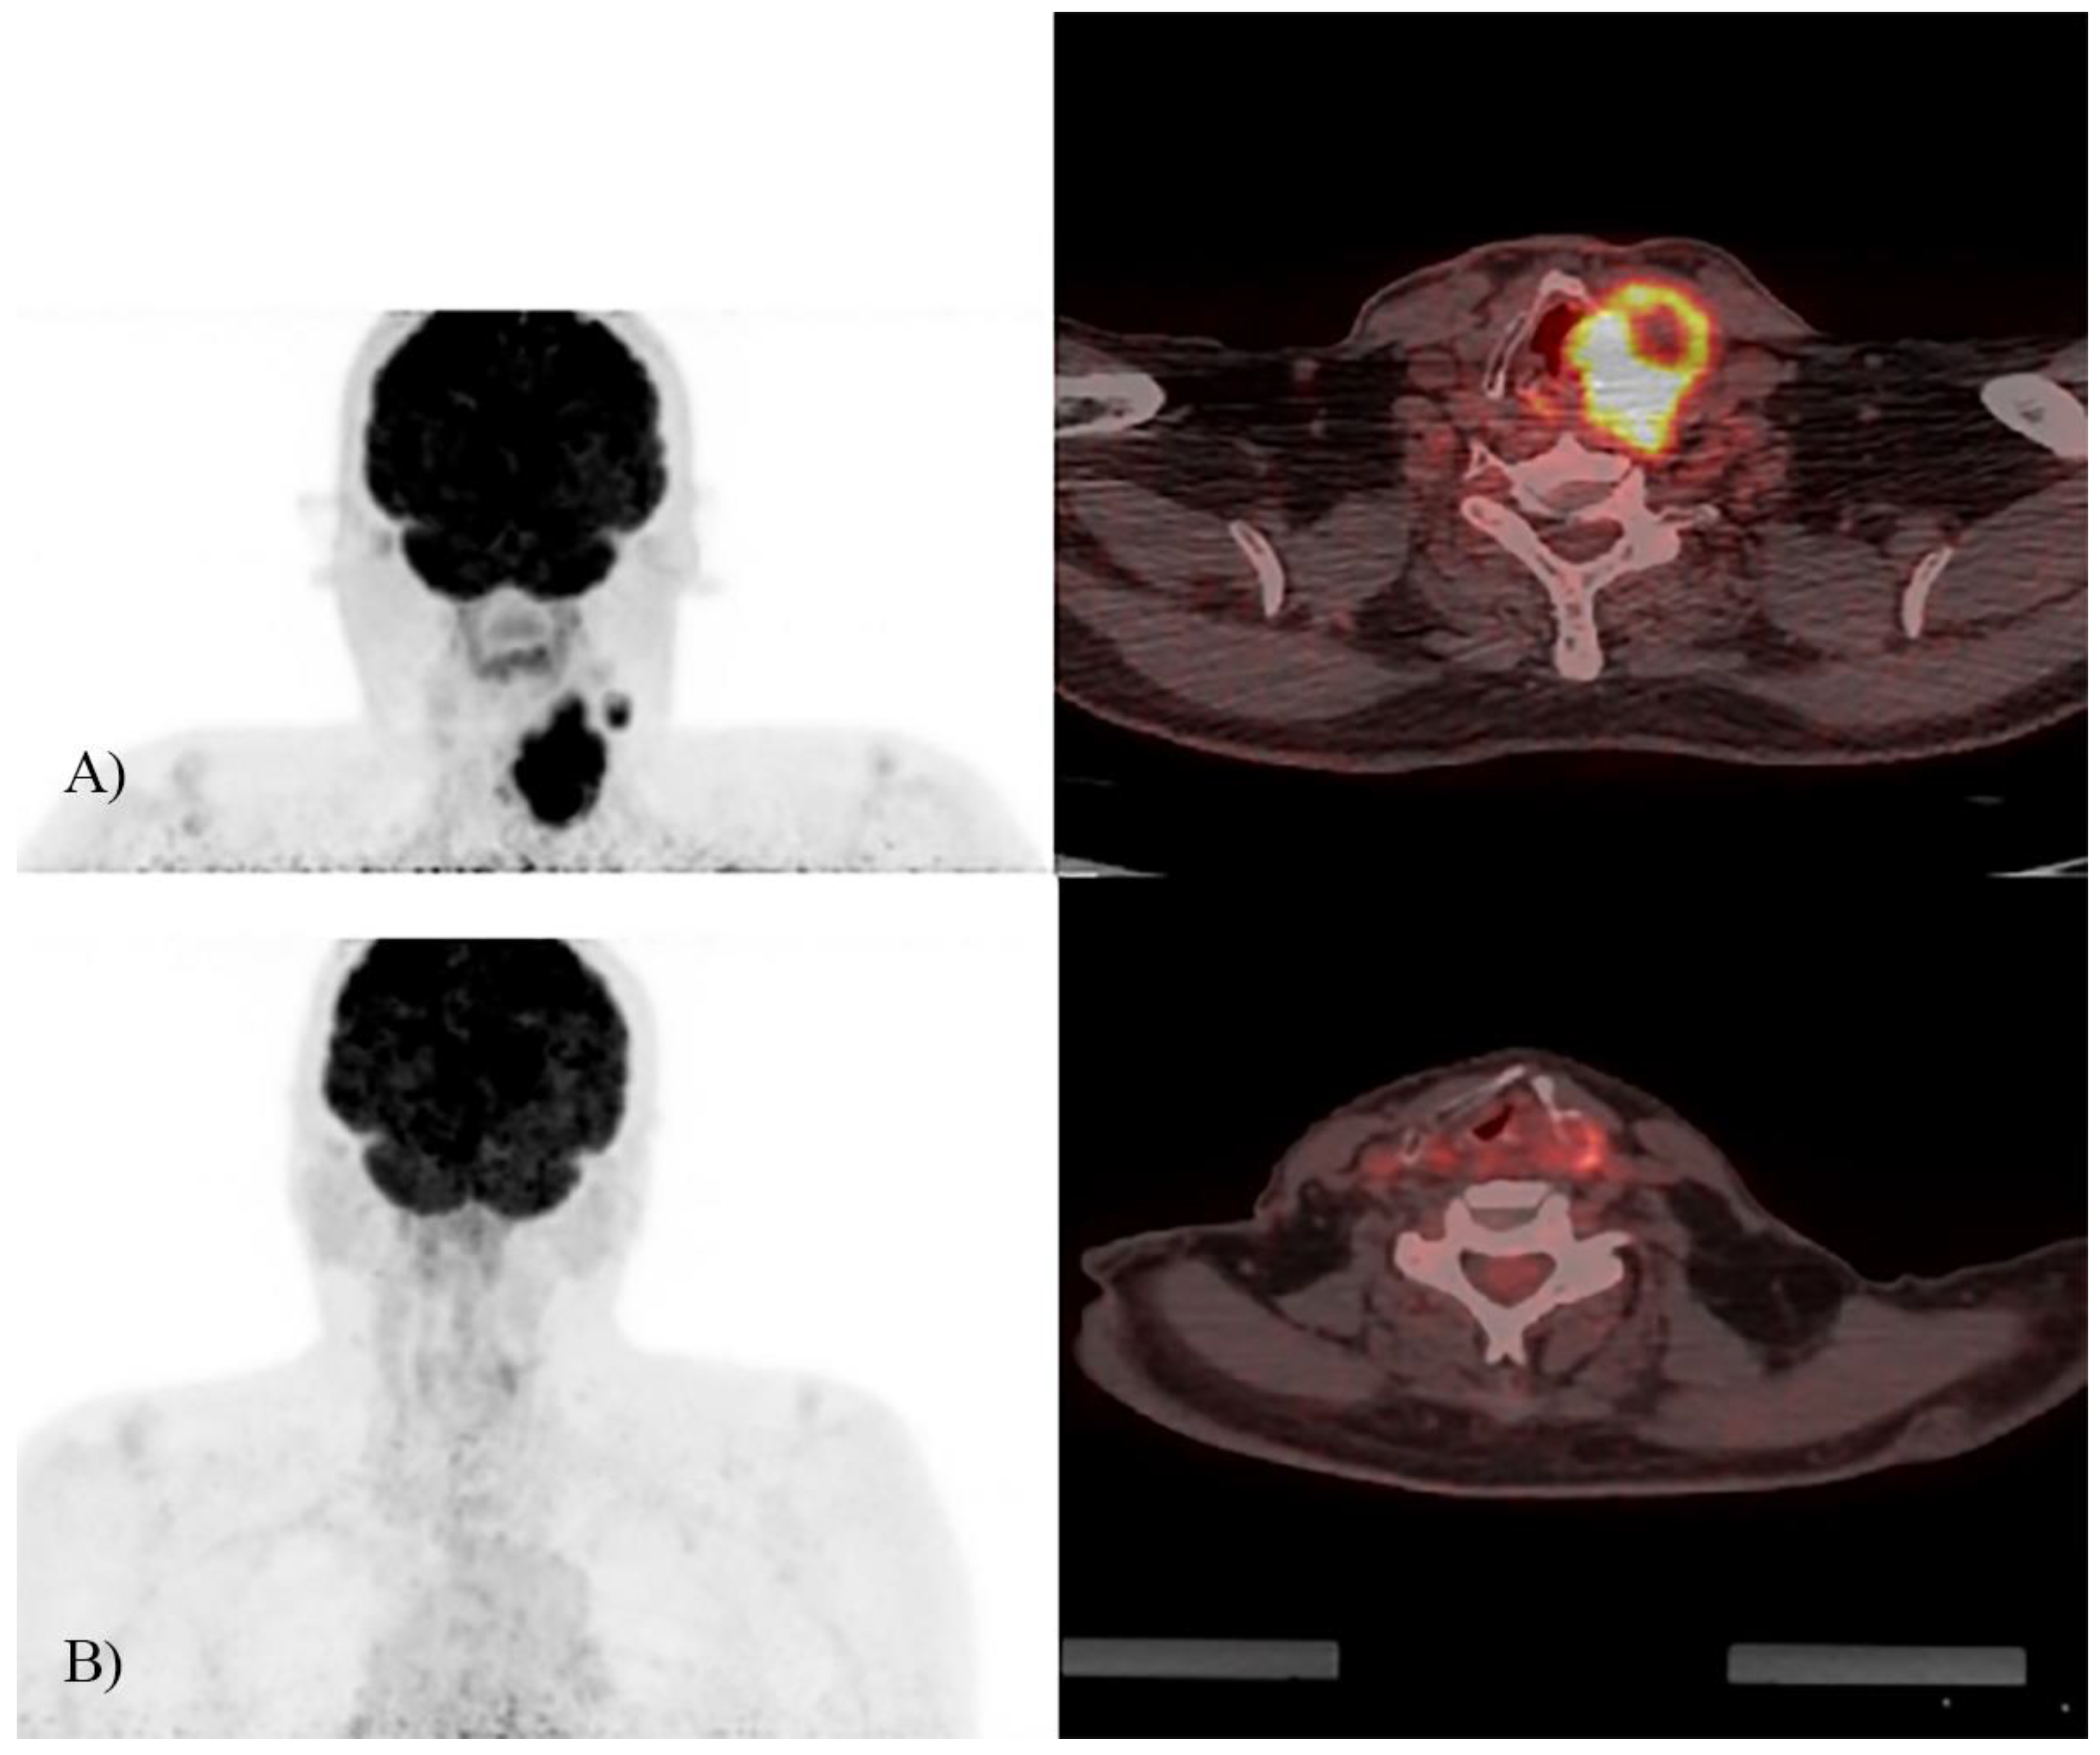

Use of 18F-FDG PET/CT Imaging for Radiotherapy Target Volume Delineation after Induction Chemotherapy and for Prognosis of Locally Advanced Squamous Cell Carcinoma of the Head and Neck